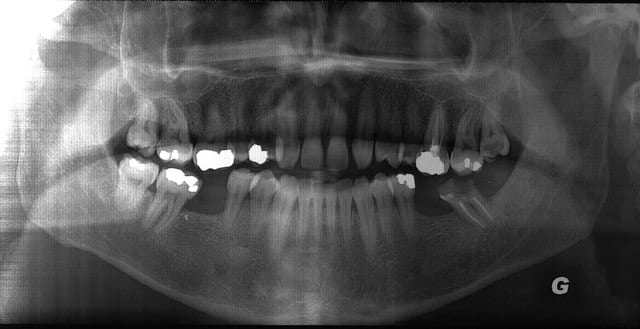

homme d'environ 40 ans se présente au cabinet pour la première fois, en urgence. Abcès au niveau de la furcation de 37. De plus, le traitement endo de cette dent baigne dans la salive depuis environ 2 ans. A l'époque, le dentiste avait réalisé l'endo et proposé la réalisation d'un bridge 35,36,37. Comme le patient n'avait pas les moyens (et plus de douleurs) il n'est jamais retourné à son rdv et est resté avec son cavit. Ayant fait quelques économies, il souhaite réaliser le bridge maintenant.

Il m'a déposé aujourd'hui la pano que je lui avais demandé, et je commence à cogiter sur ce que je vais lui proposer.(pour les grandes lignes, car il faut que je le revois en consultation pour affiner mon bilan). Au vu de la pano (que je vais tenter de joindre)et de la rétro (impossible de l'envoyer: image pas nette au niveau de la furcation en rapport avec l'abcès) la perspective d'utiliser cette dent comme pilier de bridge ne me tente guère.

secteur 1 : régularisation occlusale de 16 si egressée, voir si le soin volumineux est satisfaisant

secteur 2 : soin 15 carie mésiale, 16 retraitement + couronne pour récupérer la courbe de spee, 17 régularisation occlusale, 18 extraction

secteur 3 : extraction 37, proposition implantaire pour 36,37

secteur 4 : faire rétro alvéolaire de 45 pour niveau osseux distal, mobilité ?, proposition implantaire pour 46, avec aménagement de la face mésiale de 47

37 : Non vitale, TR baignat dans la salive depuis 2 ans, axe complètement versé, atteinte de furcation, abcès, certainement cariée au niveau de la chambre pulpaire

35: Vitale

Donc le bridge ne semble pas etre un bon choix (surtout a cause de 37)

Secteur 4 : bridge sur 2 dents vivantes dont une sans aucune obturation, pour un seul intermédiaire !!!